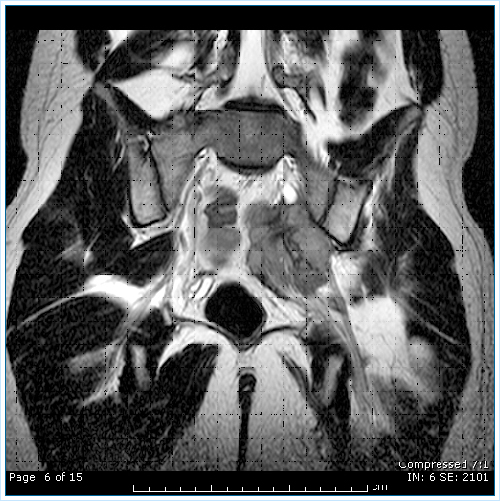

Tumor PNET comprimiendo el nervio ciatico